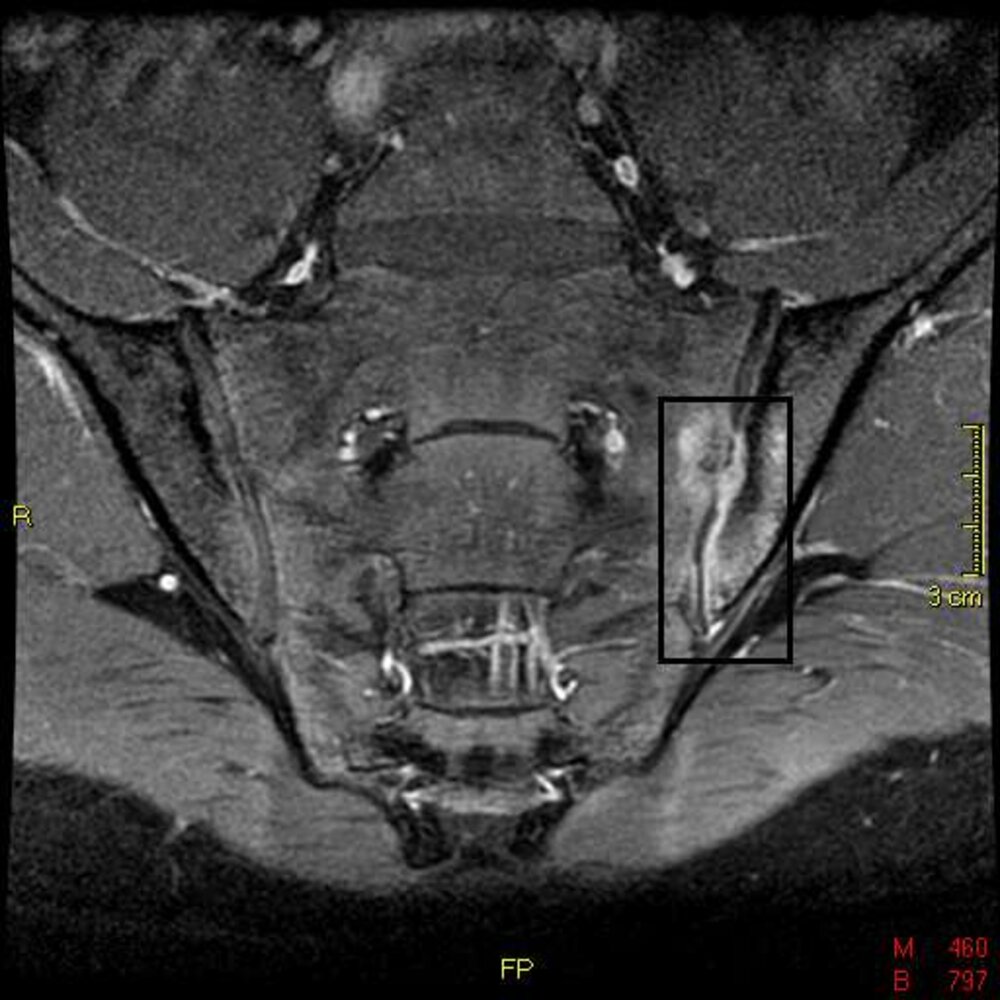

MRI

MRI is the most sensitive method for early detection of inflammatory changes of AS.However, MRI is not routinely required to confirm a diagnosis of AS as specialized MRI techniques and radiology expertise is required to accurately identify AS findings. [19]

Sacroiliac joints with gadolinium contrast

• Indication: negative or equivocal radiographs of sacroiliac joints in a patient with some classical features of AS [5]

• Characteristic findings

• Active inflammatory lesions: erosion of the sacroiliac joints and bone marrow edema (high signal intensity) [5]

• Reparative changes: secondary bone formation (low signal intensity)